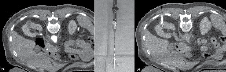

In an ideal case, there are three CT scans performed. The first CT scan is performed in the prone position using IV contrast (50% of standard dose) to plan the procedure. It is important to pay attention to surrounding structures as abdominal contents could have shifted compared to a supine CT scan. Patients with renal insufficiency can be challenging as contrast is usually avoided. Therefore, one must rely on cortical changes in the non-contrast phase to delineate the lesion, Figure 1. The trajectory of the probe is planned and measured. It is of high importance to be able to insert the probe as straight as possible (perpendicular to the skin) toward the mass. If a mass is quite medial as shown in Figure 1, it is best to plan the placement of the probe slightly lateral off the paraspinal muscles to avoid pain.

Figure 1. Non-contrast planning image of patient with renal insufficiency. Notice the cortical and contour changes that help delineate the mass. Typically, it is best to come down as perpendicular on the mass as possible. With lesions located very medial, it is best to come slightly lateral off the paraspinal muscles when planning the trajectory of the probe (dashed line) to avoid pain.